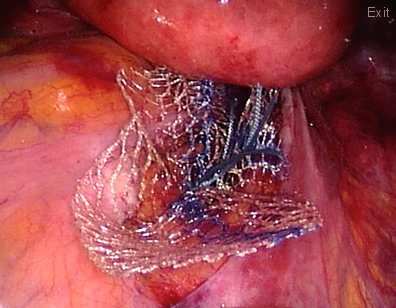

In this patient with a vaginal eversion; a mesh is attached to the vaginal vault and the vagina is pulled towards the pelvic cavity. The other end of the mesh will be attached to the sacrum bone (sacrum promontorium) to restore the normal anatomy.

The mesh is being deeply buried "between the cavity and the bones". This will avoid contact of the mesh to the bowels.